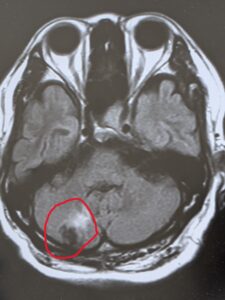

めまいで受診された方 MRIで脳腫瘍

60代男性の方です。

1週間前からめまいがあり、2つの耳鼻科に受診されました。

めまい止めを処方されました。

よくならないため、当院へ受診

MRIで小脳に脳腫瘍を認めました。